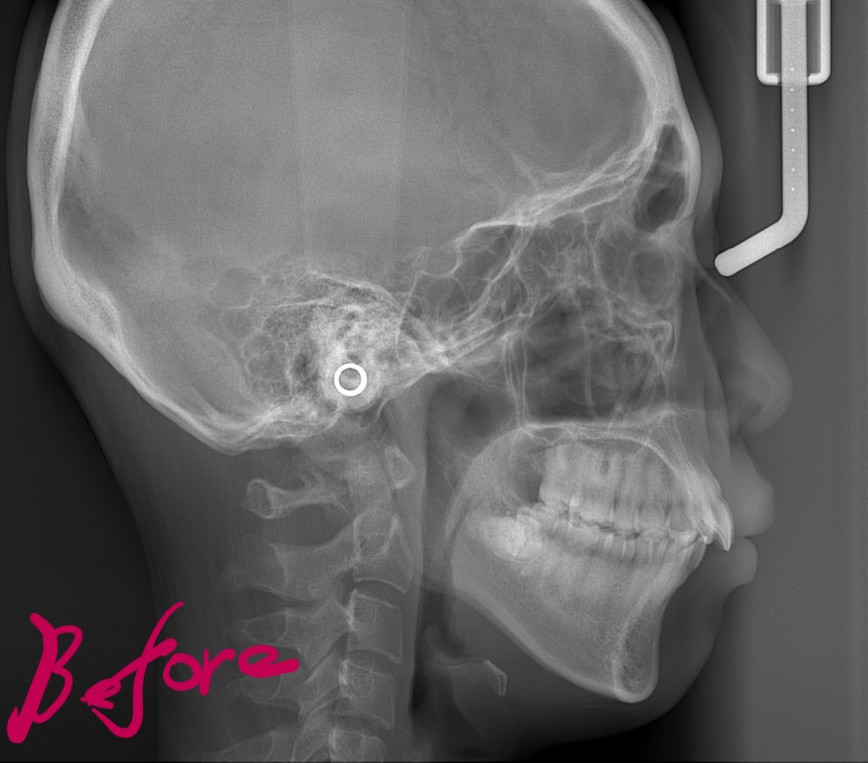

【Before】

レントゲン写真を確認すると、

この患者さんの場合、

*歯並びの写真で見ると「出っ歯」であるとは分かり難いですが、頭部全体のレントゲン写真を見ると、出っ歯であることがハッキリと分かります。

では、矯正治療前後の「レントゲン写真」や「笑顔、口元の写真」などを比較してみましょう。

まずはレントゲン写真の比較です。

左側が矯正治療前、右側が矯正治療後